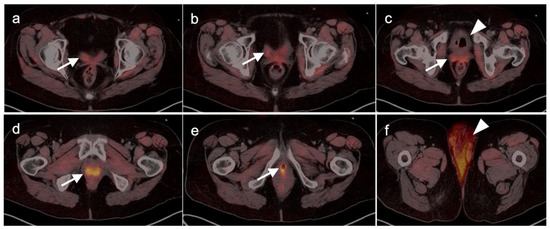

- Crivellaro, C.; Guglielmo, P.; De Ponti, E.; Elisei, F.; Guerra, L.; Magni, S.; La Manna, M.; Di Martino, G.; Landoni, C.; Buda, A. 18F-FDG PET/CT in preoperative staging of vulvar cancer patients. Medicine 2017, 96, e7943. [Google Scholar] [CrossRef]

- Oldan, J.D.; Sullivan, S.A. Positron emission tomography-computed tomography for inguinal nodes in vulvar cancer. World J. Nucl. Med. 2018, 17, 139–144. [Google Scholar] [CrossRef] [PubMed]

- Triumbari, E.K.; de Koster, E.J.; Rufini, V.; Fragomeni, S.M.; Garganese, G.; Collarino, A. 18F-FDG PET and 18F-FDG PET/CT in Vulvar Cancer. Clin. Nucl. Med. 2020, 46, 125–132. [Google Scholar] [CrossRef] [PubMed]